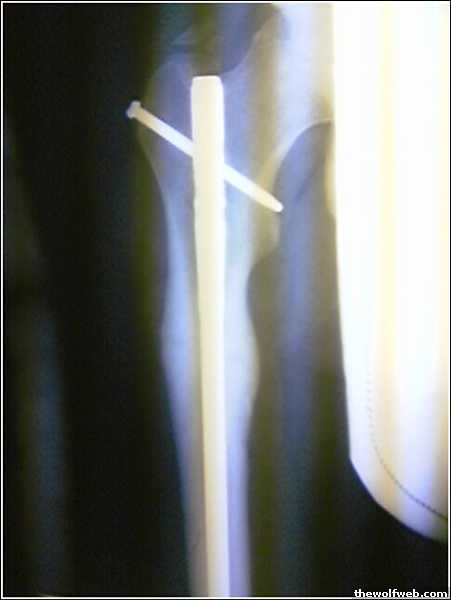

ivan, ive got a Stainless Steel rod in my right leg.

if you get a rod then we will battle.

yeah, i had a rod but they had to take it because they thought it was contributing to the infection. just a few screws in there now, and one in my other leg.

dude thats cool.

thats mine.

they said they could take it out, but im not having and problems with it. plus if they have to reverse the procedure , then hell no.

jesus that one looks bad

well that picture was 1 year after i broke it

when it happened.

the day the rod was put in

its been like 3 years now. its fully fuctional. just kinda gets annoying if ive been sitting a long time